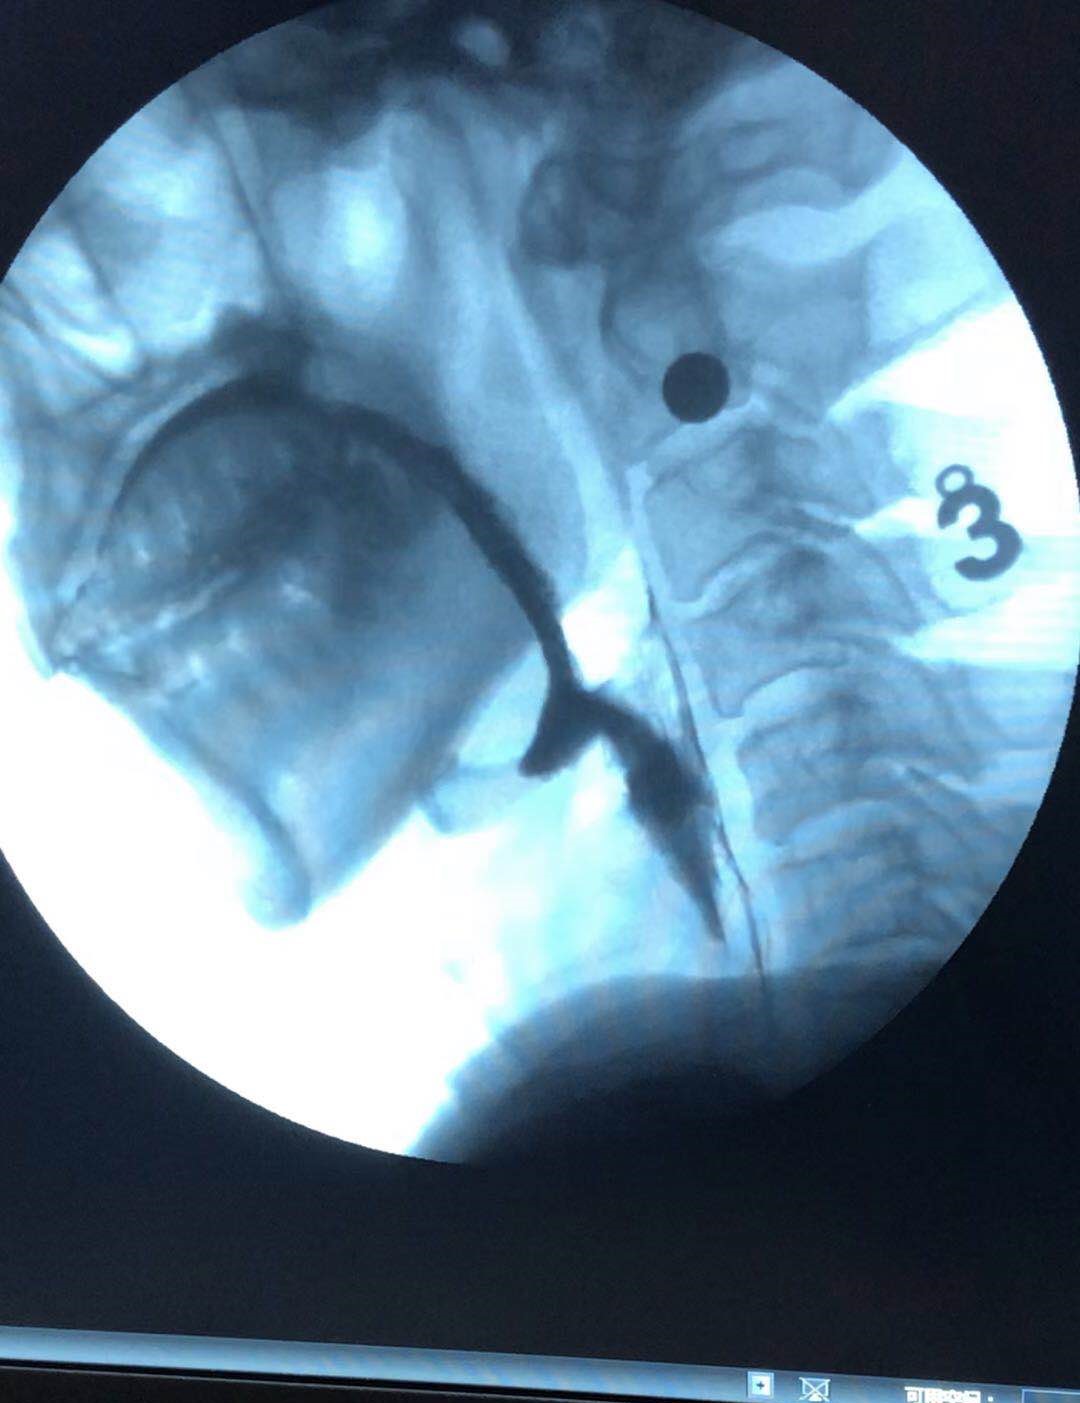

自2014年康复医学科开科以来,每年收治吞咽障碍患者200余例,在康复医师、康复治疗师、康复护士和传统的中医针灸等团队的努力下,使吞咽障碍患者疗效显著。2018年6月份以来,开展了吞咽造影检查50余例,患者经过标准化的临床评估和进一步的吞咽造影检查,使治疗师的治疗更有针对性,使患者在最短的时间得到最有效的治疗,大大提高了治愈率,使患者早日能够经口进食,享受美味。